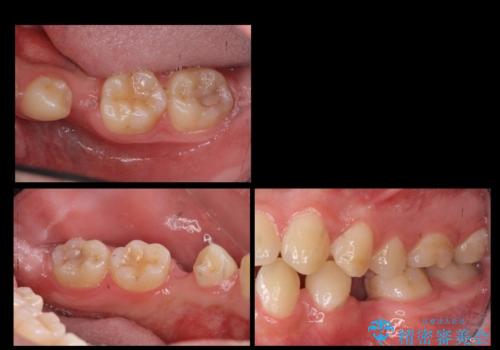

[ 臼歯部インプラント治療 ] 抜けた歯を治療したい

![[ 臼歯部インプラント治療 ] 抜けた歯を治療したいの症例 治療前](https://seimitsushinbi.jp/wp/wp-content/uploads/2022/06/b20681531f81bbbcb107d489675c3fe3-500x350.jpg?v=1655969039)

![[ 臼歯部インプラント治療 ] 抜けた歯を治療したいの症例 治療後](https://seimitsushinbi.jp/wp/wp-content/uploads/2022/06/3d94cd3d2c3bb38c4cb75b95fbdde67e-500x350.jpg?v=1655972093)